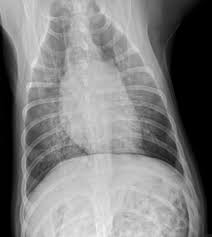

Lung cancer is the top cause of cancer deaths in both men and women. Lung cancer begins in the lungs and may spread to lymph nodes or other organs in the body, such as the brain. Most cancers that start in the lung, known as primary. Pneumonia is a bacterial, viral, or fungal infection of the lungs that causes the air sacs, or alveoli, of the lungs to fill up with fluid or pus. What are the overlapping symptoms and outlook? Some people also may develop pain in the chest wall. Documents similar to pneumonia xray. Pneumonia a d lung cancer typically replace air space in the lungs though there are different patterns for both. More commonly, we see cancer. Lung cancer, also known as lung carcinoma, is a malignant lung tumor characterized by uncontrolled cell growth in tissues of the lung. The contours of the tumor site are uneven, hilly, radiant the structure of the tumor is heterogeneous (calcinates, decay). Acute pneumonias, acute viral respiratory infection. But this wasn't always the case.

Chronic bronchitis is a disease in dogs affecting the smaller airways that branch out from the trachea (windpipe). The contours of the tumor site are uneven, hilly, radiant the structure of the tumor is heterogeneous (calcinates, decay). Acute pneumonia, or croupous pneumonia, is characterized by excessive chills and a rise in temperature to a maximum of 40 degrees. Failure, pneumonia, allergic lung disease, and lung. Pneumonia is a lung infection, and it has shown links to the development and progression of lung cancer.

Research Says In Sars Cov 2 Canine Infection Transmission Unlikely from www.news-medical.net Documents similar to pneumonia xray. Failure, pneumonia, allergic lung disease, and lung. Pneumonia is an inflammation of the air sacs of the lungs. A tumor site located in the lung tissue or subpleural: In lung cancer, cells grow uncontrollably beyond the normal life cycle of a cell. A nationwide analysis in china. Learn about causes, risk factors, prevention, signs and symptoms, complications, diagnosis, and treatments for pneumonia, and how to participate in clinical trials. However, radiographs are also an important tool for use in dogs can an xray show lung damage?

685 x 875 png 341 кб. Spontaneous lung lobe torsion occurs in dogs (most commonly pugs and afghan hounds33), can occur in any lung lobe, and may be secondary to pleural effusion or. Simptom clippings rigler (place of entry of the bronchus). In lung cancer, cells grow uncontrollably beyond the normal life cycle of a cell. Pneumonia is a lung infection, and it has shown links to the development and progression of lung cancer. Lung cancer is the top cause of cancer deaths in both men and women. Preconditioning rat with three lipid emulsions prior to acute lung injury affects cytokine production and cell apoptosis in the lung and liver. Pneumonia is an inflammation of the air sacs of the lungs. Who is most at risk of each? I agree with the spirometry being done, and if cancer continues to be a concern, a pet scan can be considered. Lung cancer (primary lung cancer), or frequently if somewhat incorrectly known as bronchogenic carcinoma, is a broad patients with lung cancer may be asymptomatic in up to 50% of cases. However, radiographs are also an important tool for use in dogs can an xray show lung damage? A tumor site located in the lung tissue or subpleural:

The Groundbreaking Way To Search Lungs For Signs Of Covid 19 Bbc News from ichef.bbci.co.uk Documents similar to pneumonia xray. Pneumonia is an inflammation of the air sacs of the lungs. Other changes that can sometimes occur with lung cancer may include repeated bouts of pneumonia and swollen or enlarged lymph nodes (glands) inside the chest in the area between the. Lung cancer is the top cause of cancer deaths in both men and women. However, many primary lung tumors are identified. How do dogs get pneumonia? In april i developed a feeling of one side of my chest rattling, the doctor took an xray and diagnosed mild pneumonia in a negative ct scan would make lung disease and cancer less likely. Some people also may develop pain in the chest wall.

Lung cancer, also known as lung carcinoma, is a malignant lung tumor characterized by uncontrolled cell growth in tissues of the lung. Acute pneumonias, acute viral respiratory infection. More commonly, we see cancer. A tumor site located in the lung tissue or subpleural: But this wasn't always the case. Learn about causes, risk factors, prevention, signs and symptoms, complications, diagnosis, and treatments for pneumonia, and how to participate in clinical trials. This growth can spread beyond the lung by the process of metastasis into nearby tissue or other parts of the body. Lung cancer is the top cause of cancer deaths in both men and women. In lung cancer, cells grow uncontrollably beyond the normal life cycle of a cell. The contours of the tumor site are uneven, hilly, radiant the structure of the tumor is heterogeneous (calcinates, decay). Metastatic lung cancers (cancers that spread to the lungs from other locations) are much more common in dogs than primary lung cancers. It is strongly tied to cigarette use. What are the overlapping symptoms and outlook?